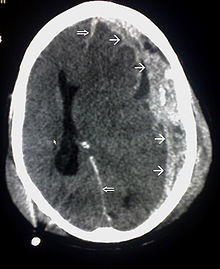

Brain trauma CT.jpg

CT scan showing cerebral contusions, hemorrhage within the hemispheres, subdural hematoma, and skull fractures[2]